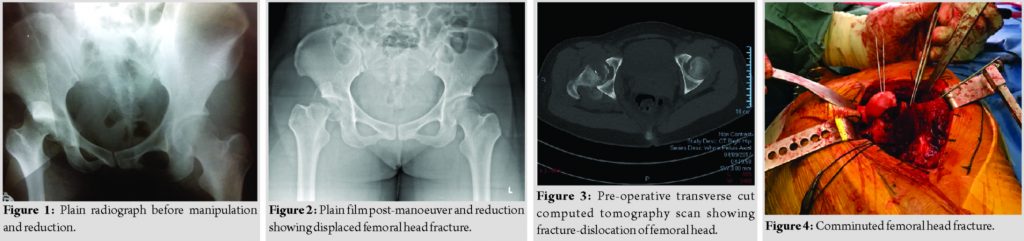

A 35-year-old female who was training for a downhill running race was running at high-speed down a hill when she tripped over a log of wood and fell forward. She subsequently complained of severe pain in her right hip and was unable to mobilize. When brought to the local hospital, plain radiograph showed a right posterior hip dislocation associated with a femoral head fracture (Fig. 1). Manipulation and reduction (M and R) were attempted, approximately within 6 h to injury, to relocate the right hip and subsequent post M and R radiographs showed iatrogenic fracture of the femoral neck (Fig. 2). She was subsequently transferred to our center for further care. On arrival, it was 48 h from the time of her injury. An urgent computed tomographic scan was done which showed a fracture-dislocation of the right hip (Fig. 3). She underwent an open surgical dislocation of the hip and internal fixation of the femoral head that same day.

As per a standard Ganz’s osteotomy [6], with the patient placed in a lateral position and through Hardinge approach, we performed a trochanteric osteotomy flipping the osteotomized trochanteric fragment anteriorly. Ganz’s osteotomy was preferred as it allowed for full exposure of the femoral head conferring advantages in fracture reduction [6] and compared to the anterior and posterior approach had the lowest risk of avascular necrosis [4]. This approach allowed for Z-shaped anterosuperior capsulotomy to dislocate the femoral head for visualization and fixation of the fracture. The fracture line ran inferior to the fovea separating a main superior and grossly comminuted inferior fragment (Fig. 4 and 5). The largest femoral head fragment was fixed to the femoral neck with two 6.5mm Depuy Synthes (Depuy Synthes, Warsaw, IN) headless compression screws and the remaining femoral head fragments were reconstructed using4.5mm headless compression screws. The femoral head was then reduced within the acetabulum and the trochanteric flip osteotomy was fixed usingheadless and cortical screws (Fig. 6). Post-operative X-rays of the hip demonstrated good reduction of the femoral head and neck fracture. Rehabilitation was started immediately after surgery. She was kept on non-weight-bearing of the operated limb for 6 weeks with gradual increase in weight-bearing thereafter with eventual full weight-bearing status at 3 months post-surgery. Four months after surgery, the patient complained of persistent right hip pain with ambulation and was unable to wean off her crutches. Plain radiographs showed avascular necrosis of the femoral head with progressive shrink and collapse (Fig.7), resulting in prominent compression screws abutting against the acetabulum. Given the clinical picture, we counseled the patient for the removal of implants and conversion to the right total hip arthroplasty (Fig.8).The patient underwent surgery uneventfully. Rehabilitation was started immediately in the post-operative period. At 12 months following surgery, plain radiographs were satisfactory and the patient could ambulate freely without pain.